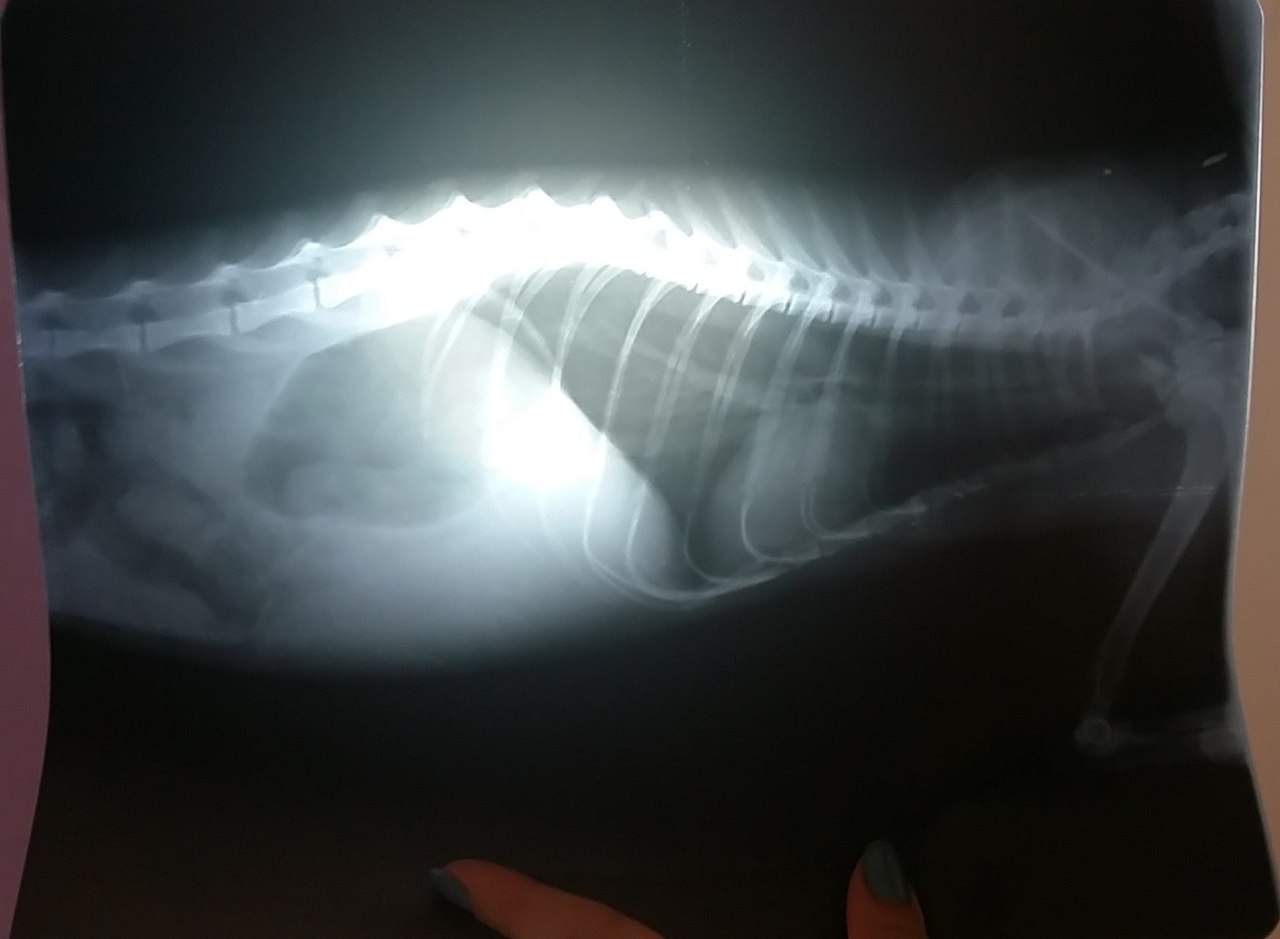

#нужна_финансовая_помощь@vmestepnz_animalsНУЖНА ФИНАНСОВАЯ ПОМОЩЬ СЕРОМУ⚡ Необходимо: 5222.30 рублей ⚡ Собрано: 1652.40 рублей (32%)Помочь Серому animals-pnz.ru/personal_pay?animal_id=28г.ПензаМолодой и умненький котик, очень ласковый. К лотку приученНаш Серый был в поиске нового дома, но серьёзно заболел. Стал плохо есть с позывами к рвоте, желтушные кожные покровы и слизистая, котик очень вялый.При посещении ветеринара сделано узи, общий анализ крови, оказались серьёзные проблемы с печенью, расширение желудка, подозрение на непроходимость. Назначено дорогостоящее лечение и нам без вашей помощи просто не вытянуть его…Лекарства нам дали добрые и неравнодушные люди. Но все анализы очень дорогие. Еще предстоит один рентген с контрастным веществом. Продолжение лечения и повторные анализы предстоят у нас в скором времени.Без помощи мальчишка погибнет. 4.4.2018: Посещение клиники. Общий анализ крови и биохимия, рентген — расширение желудка, подозрение на непроходимость. 7.4.2018: Посещение клиники. Рентген с контрастным веществом — обнаружен посторонний предмет. Сильное расширение кишечника. 20.4.2018: Посещение клиники. Рентген брюшной полости с контрастным веществом. Ранее выявленный посторонний предмет на данном снимке не просматривается.Кишечник менее расширен. 22.4.2018: Посещение клиники. Ранее выявленный посторонний предмет на рентгене от 20.04.18 не просматривается, но прощупывается в тазовой области. Назначено вазелиновое масло в течении 2-х недель и повторный рентген. Так же через 2 недели повторная биохимия.Живот на ощупь гораздо лучше и практически нет желтизны. 6.5.2018: Посещение клиники. Рентген. Посторонний предмет не просматривается. Расширение желудка, затенение эпигастральной области. Под вопросом панкреатит. 7.5.2018: Посещение клиники. Посторонний предмет по-прежнему прощупывается в тазовой области. Отек прямой кишки. Назначен фуросемид и вазелиновое масло. Помочь Серому animals-pnz.ru/personal_pay?animal_id=28История: animals-pnz.ru/animals/cats/28Фин.отчет: animals-pnz.ru/reports/animal/28Куратор: Галина vk.com/id22648687, ☎ +79053660321